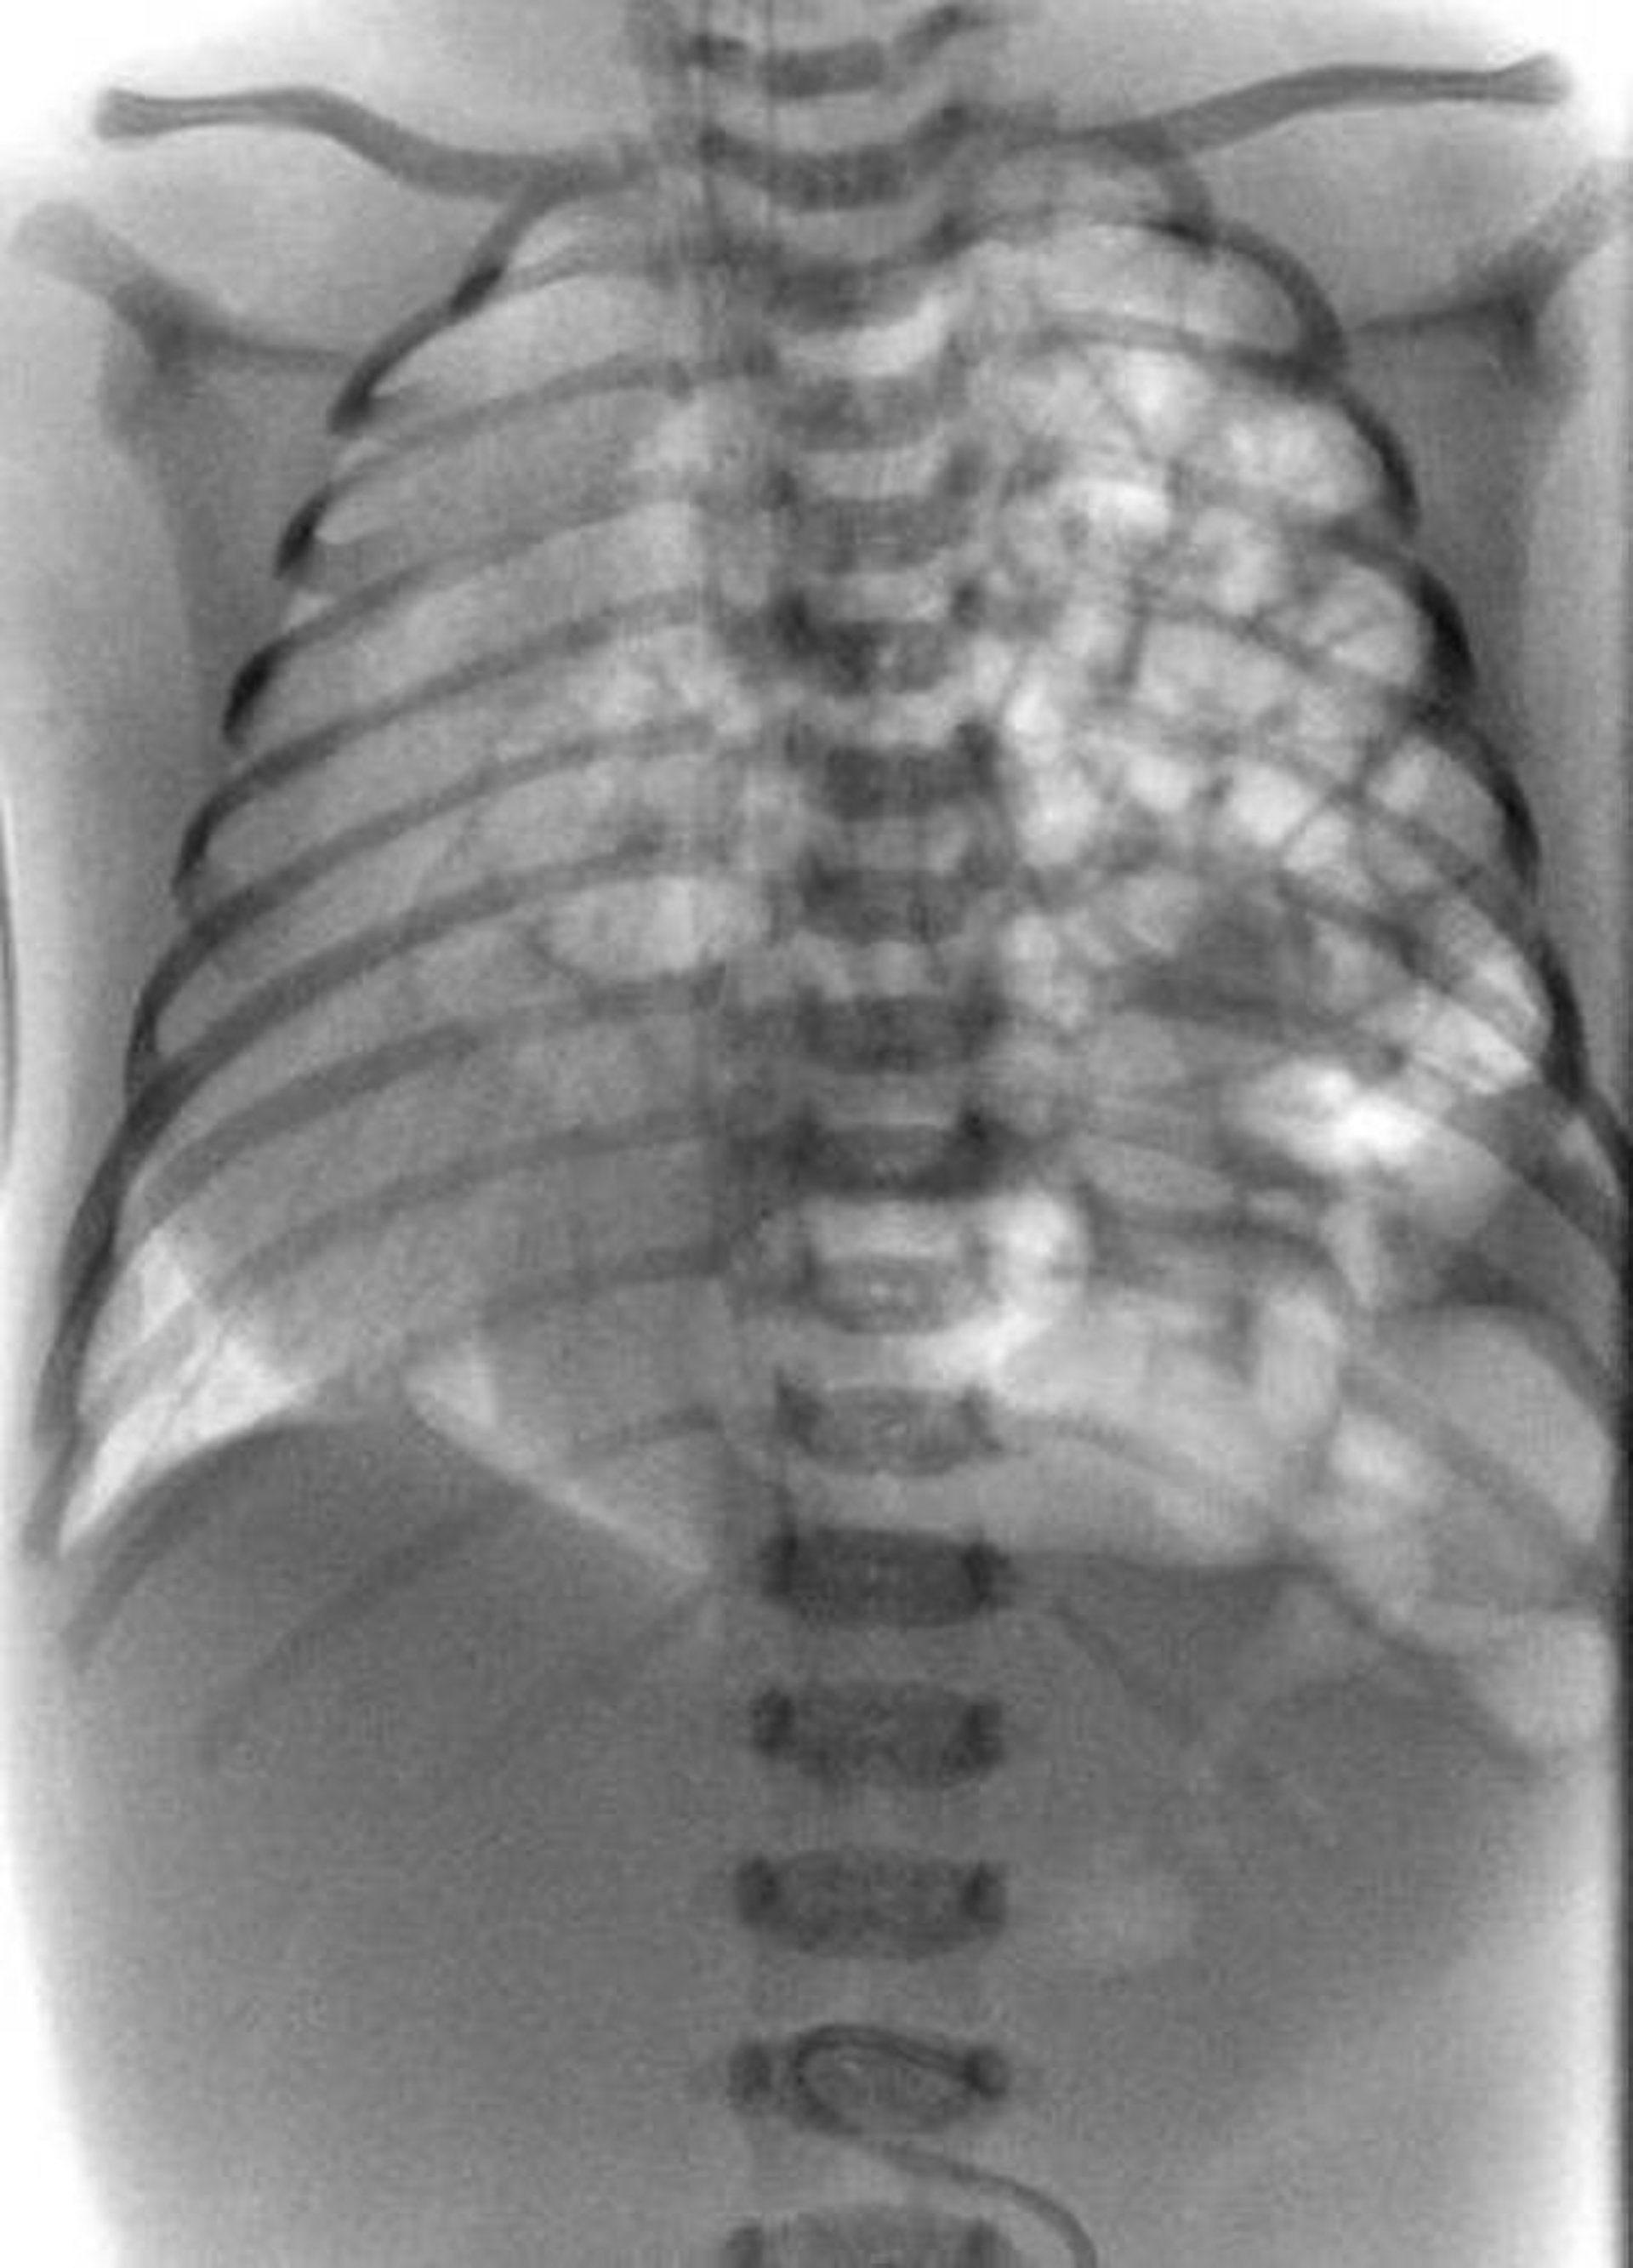

This radiograph shows congenital diaphragmatic hernia in a neonate. Loops of bowel are protruding into the left chest (right side of radiograph).